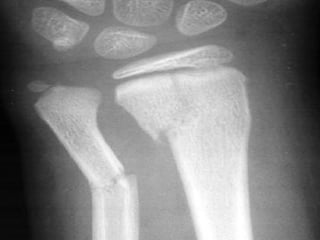

LOCALIZACION Diafisiaria Metafisiaria Epifisiaria Intraarticular Fractura-luxación

LOCALIZACION Diafisiaria MetafisiariaEpifisiaria Intraarticular Fractura-luxación